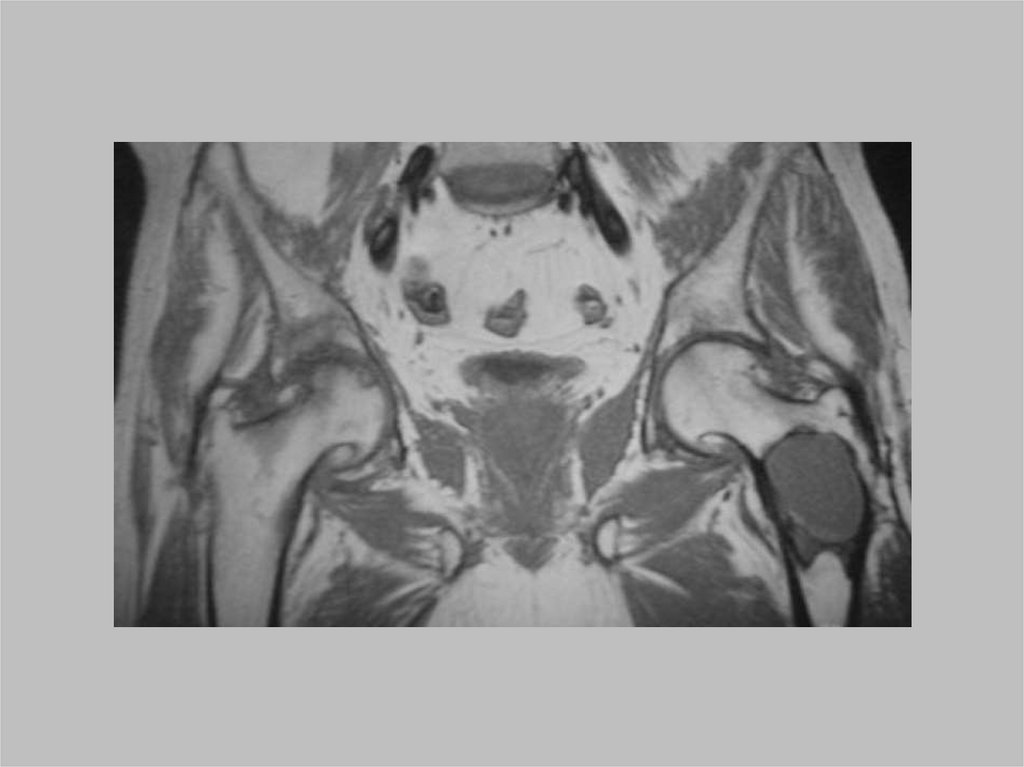

Дисплазия тазобедренного сустава

чаще встречается у женщин, чем у

мужчин (от 5:1 до 9:1 соответственно).

До 30% случаев являются

двусторонними.

Раннее выявление и компенсация

могут привести к нормальному

развитию в 95% случаев.

63.

Рентгенограммы:

• меньше ядро окостенения головки бедренной кости,

• верхнелатеральное смещение бедренной кости.

• в норме угол вертлужной впадины: 28 градусов при рождении, а далее

уменьшается к 1 году до 22 ± 5 градусов (при дисплазии тазобедренного сустава

угол увеличен).

• Линия Шентона образует плавную дугу вдоль верхней ветви лобковой кости и

шейки бедра в норме. При дисплазии тазобедренного сустава данная дуга

прерывается.

• Линия Перкина перпендикулярна линии Хильгенрайнера (линии, проходящей

через трехлучевой хрящ). Это делит бедро на квадранты. Головка бедренной

кости или медиальный метафизарный «клюв» должны располагаться в нижнемедиальном квадранте.

• Указанные признаки становятся более очевидными при взрослении ребёнка.